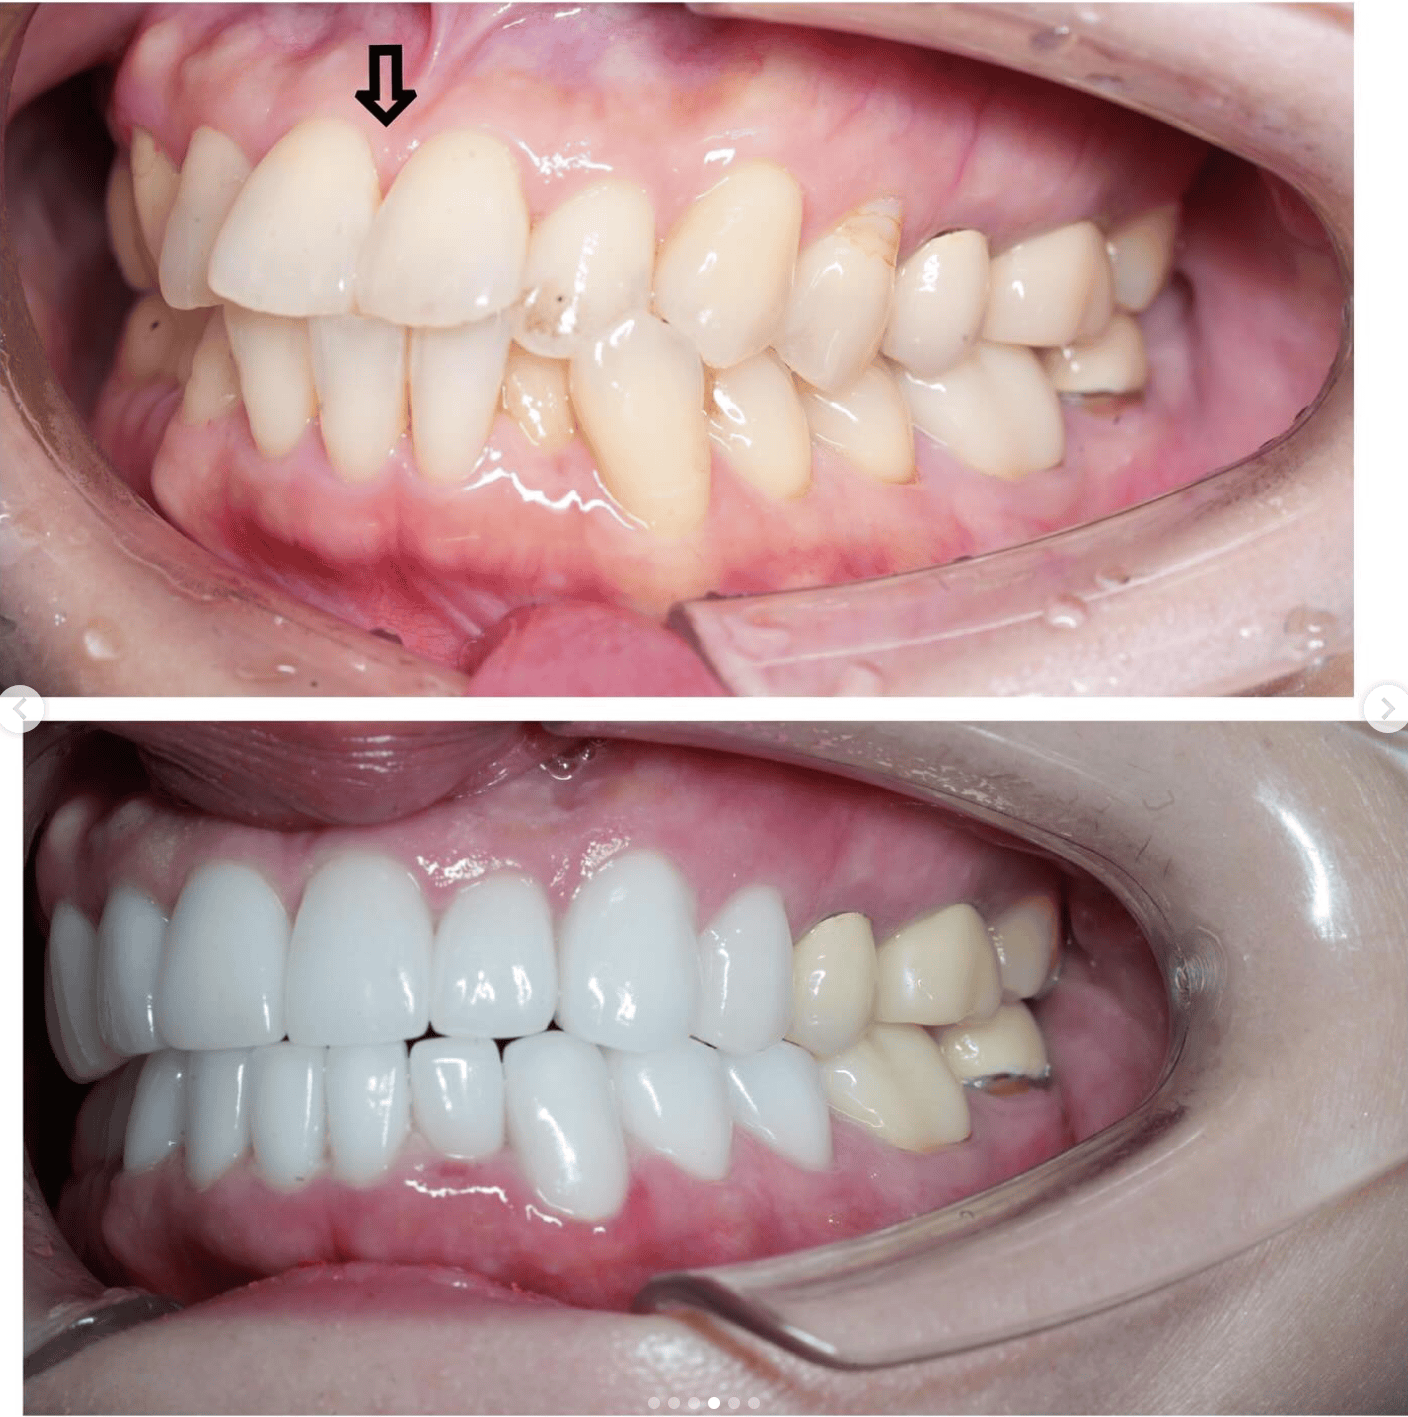

Case022 – インプラント

広島からの患者様です。

前歯を綺麗にしたい。インプラントをしたい。

という主訴で東京の歯医者をいろいろ調べて当院を選んでくださいました。

毎回、遠い中しっかり通ってくださり、選んで頂けた嬉しさと、その気持ちに応えたいという想いで診療させて頂きました。

前歯はご希望のお色でラミネートベニアでは出せない透明感のあるセラミックに上下左側7はインプラントをさせて頂きました。

左上は破折で温存不可。

骨も少なかったので、サイナスリフトも行い計五回の来院で被せ物を入れさせて頂きました。

左下は前回のクリニックでの埋入位置が深すぎて食べカスも毎回詰まる、セルフメンテナンスではら汚れも取れない。インプラント周囲炎にもなっていたので、一度前のインプラントを除去し、そこから新しくインプラントを埋入し、診療させて頂きました。

インプラント、歯並び、審美歯科にご興味のある方はいつでも相談にお越しください。

担当 理事長 佐藤 悠野